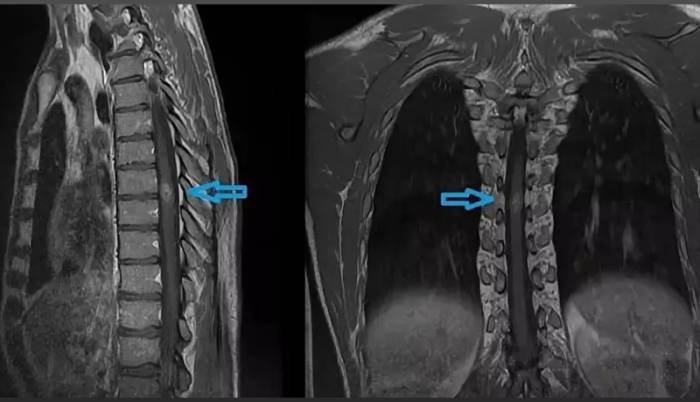

Опухоль спинного мозга на МР-томограмме (обозначена стрелкой)

На МР-изображении стрелками показан ушиб шестого грудного позвонка (визуализируется отек костных структур без деформации тела позвонка)